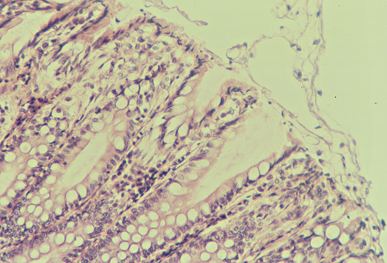

Autolyse post-mortem (diapo 1)